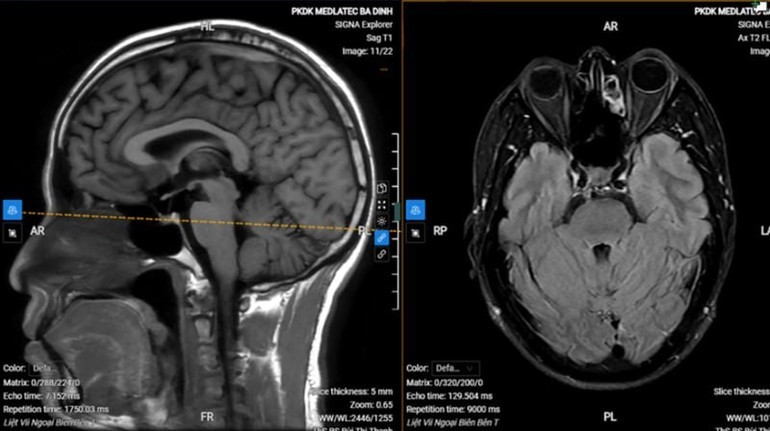

Chụp MRI sọ não cho thấy hình ảnh thoái hóa myelin chất trắng dưới vỏ bán cầu đại não bên hai bên (phân loại Fazekas độ 1), không thấy tổn thương cấp tính nội sọ.

Với kết quả trên, anh S. được chẩn đoán liệt dây thần kinh số VII ngoại biên trái vô căn (liệt Bell). Bệnh nhân được kê đơn điều trị ngoại trú, hướng dẫn tập các bài tập cơ vùng mặt, chăm sóc mắt, phối hợp châm cứu sau 1 tuần.

image-2026-01-03t105650028-1767412626.jpg

Hình ảnh chụp MRI của bệnh nhân.